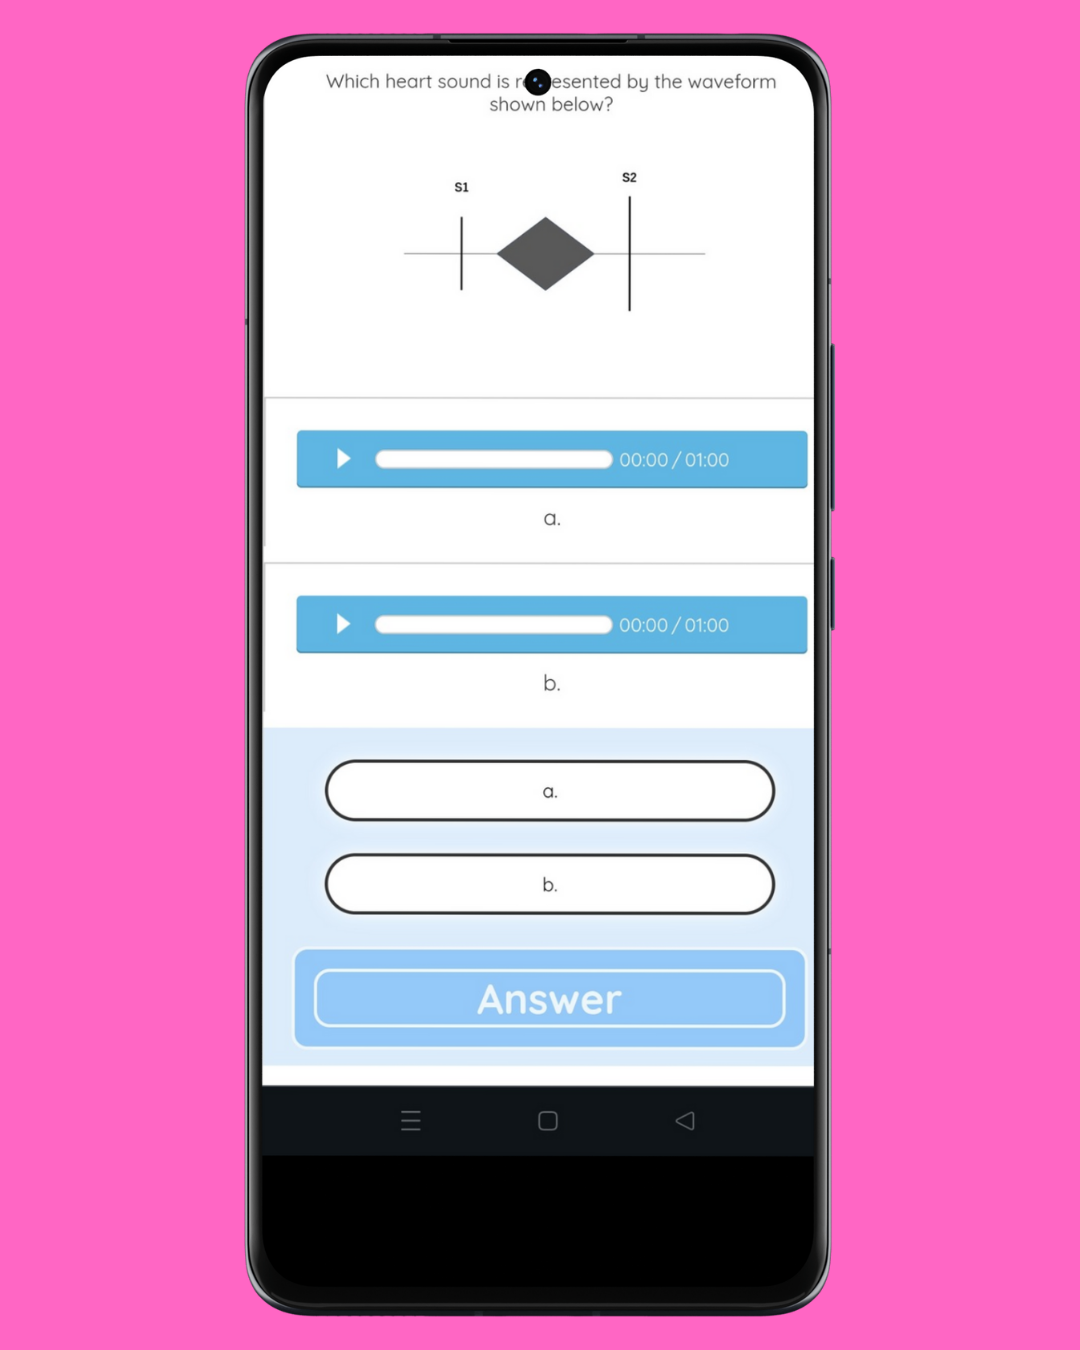

On May 4, the quiz involves listening to two heart murmurs and selecting the matching phonocardiogram. It is necessary to distinguish between a mid-systolic murmur and a holosystolic murmur. (May 4, 2025)

On May 4, the quiz involves listening to two heart murmurs and selecting the matching phonocardiogram. It is necessary to distinguish between a mid-systolic murmur and a holosystolic murmur.

※ Use earphones.